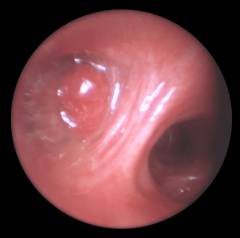

6. Бронхоскопия

Это инвазивный метод исследования дыхательных путей с помощью бронхоскопа.

Преимущества:

• выявление опухоли, воспалительных процессов и инородных тел в бронхах;

• возможность взятия биопсии опухоли.

Недостатки:

• инвазивность и неприятные ощущения при проведении процедуры.

Показания:

• подозрение на новообразование в бронхе;

• взятие биопсионного материала ткани.